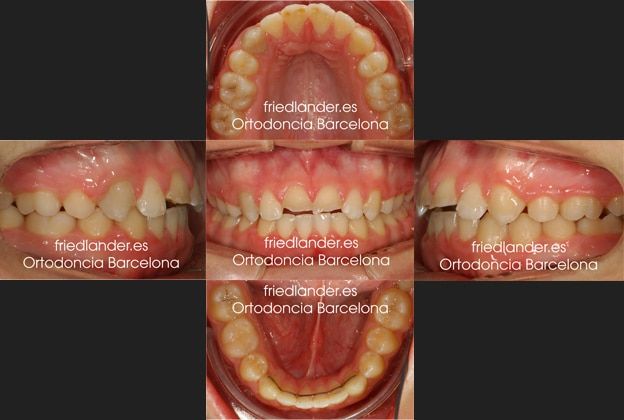

El tratamiento fue planteado con extracciones para poder cerrar la mordida, mejorar la clase II y solucionar el apiñamiento. El plan de tratamiento consistió en extracciones asimétricas en la mandibular extrayendo el primer premolar inferior en el lado derecho y en el izquierdo extraer el primer molar con la enorme caries que presentaba y la retracción de los dientes con microtornillos. Aunque ortodócicamente hubiera sido más fácil hacer extracciones simétricas, en este caso al tener un diente que requiere una endodoncia decidimos extraer éste y no un diente sano.

El resultado después de 24 meses de tratamiento con ortodoncia de autoligado. Se puede ver que nivelamos los márgenes gingivales para facilitar la rehabiliatación estética.

Al terminar la ortodoncia, los dos incisivos centrales fueron rehabilitados estéticamente con unas coronas de cerámica e-max.